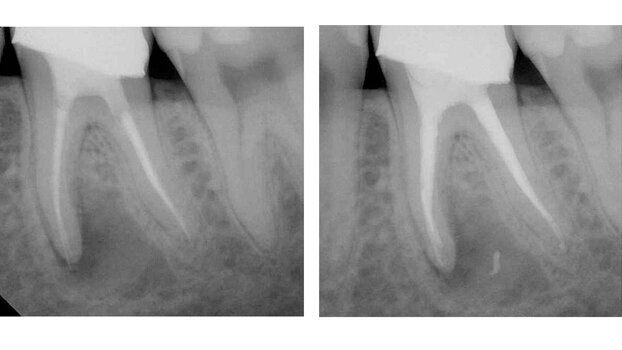

Fig 1a, 1b: Clinical cases treated in the manner described. The Twisted File (SybronEndo, Orange, CA, USA) was used to remove the plastic Thermafil Carriers (Dentsply Tulsa Dental Specialties, Tulsa, OK, USA).

Usually, it will take approximately two TF instruments (or one) to machine a plastic carrier out of the canal. When the carrier has been machined through and the clinician reaches the apex, if a film is taken, usually, the clinician can see small fragments of the carrier at the lateral root walls of the canal.

Use of solvents (most often chloroform) and Hedström files to tug these fragments out of the canal is simple, predictable and can render the entire canal free of any substantial gutta-percha or remnants of the plastic carriers. After carrier removal, optimally, the clinician would gauge the minor constriction of the apical foramen (use a hand K file to determine the initial diameter of the MC) and then finalize the preparation to the master apical diameter.